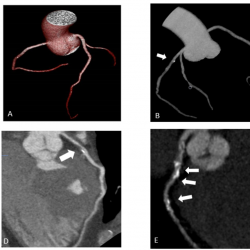

Fig. 2

Coronary arteries’ scanning images (Group 2 – obese patients).

A – Coronary arteries’ 3D reconstruction. Patient’s BMI 32.5 kg/m2; 100-kV; Effective dose 1.8 mSv.

B – Coronary arteries’ 3D reconstruction. Patient’s BMI 31.2 kg/m2; 100-kV; Effective dose 1.6 mSv; Calcified plaque in LAD S6 (labelled by white arrow).

C – Multiplanar curved reconstruction of LAD coronary artery. LAD S6 mixed plaque (labelled by white arrow), 30% stenosis. Patient’s BMI 32.5 kg/m2, 100-kV.

D – Multiplanar curved reconstruction of LAD coronary artery. LAD S6 mixed plaque (labelled by white arrow), 75% stenosis. Patient’s BMI 32.5 kg/m2, 100-kV.

E – Multiplanar curved reconstruction of LAD coronary artery. LAD S6, S7, S8 multiple calcified plaque (labelled by white arrow), stenosis 50–95%. Patient’s BMI 32.7 kg/m2, 100-kV.

F – Multiplanar reconstruction of LAD coronary artery. LAD S7 non calcified plaque (labelled by white arrow), stenosis 50%. Patient’s BMI 30.5 kg/m2, 120-kV

A total of 856 segments were qualitatively assessed: 184 segments [80-kV] versus 248 segments [100-kV] in the overweight patients group and 200 segments [100-kV] versus 224 segments [120-kV] in the obese patients group. There were no statistically significant differences in subjective image quality assessment between the two groups. As seen in data represented in Table 2, all segments were deemed as diagnostic, with an overall diagnostic image quality of 100% and no artifacts observed. We performed a comparison of qualitative image quality by two independent observers and the results showed perfect agreement with ICC of 0.8. As shown in Fig. 2, the image quality regarding noise and opacification in the obese group with ultra-low kV was not significantly altered, it maintained the possibility to identify the structure of plaque – calcified, non-calcified, multiple calcified, mixed, and defined stenosis grade.